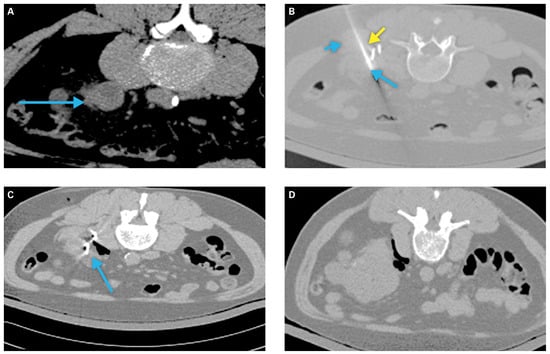

Hydrodissection via saline instillation and intentional patient positioning can increase the distance between adjacent structures and the tumor target[34] (Figure 1). Retrograde pyeloperfusion can be similarly used to protect the ureter and ureteropelvic junction from thermal injury, with resultant risk for perforation, urine leak, and/or subsequent stricture[34]. Renal tumor scoring systems can aid preprocedural planning and tumor selection[36,37].

Figure 1.

Example of a patient requiring tissue displacement prior to ablation.